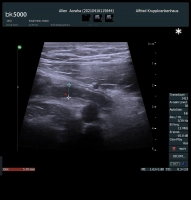

Eine akute Appendizitis kann je nach Ausprägungsgrad in eine unkomplizierte und eine komplizierte Appendizitis eingeteilt werden. Nach der EAES (European Association of Endoskopic Surgery) ist eine unkomplizierte Appendizitis eine Entzündung der Appendix ohne Hinweis auf Gangrän, Umgebungsphlegmone, freier purulenter Flüssigkeit oder Abszess.

Die Einteilung einer akuten Appendizitis in die unkomplizierte oder komplizierte Form soll prätherapeutisch vorgenommen werden, um eine adäquate Therapie auszuwählen.